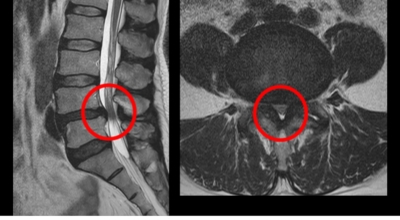

요추관 협착증은 척추 내 신경이 지나가는 통로가 좁아지는 현상으로 기인해서 신경이 눌리면서 이에 따른 여러가지 증상을 유발하는 질환을 의미해요.

허리 협착증은 척추관이 좁아지게 되면서 신경을 압박하게 되어 허리통증과 또한 다리에도 여러가지 증상을 일으키게 되는데, 발생 원인은 주로 노화로 인한 퇴행성 변화가 많았지만 요즈음는 옳지 않은 자세로 오랫동안 앉아있는 사람들이 많아지면서 생기는 경우도 많아졌으며, 선천적인 요인으로 나타나는 경우도 있답니다.